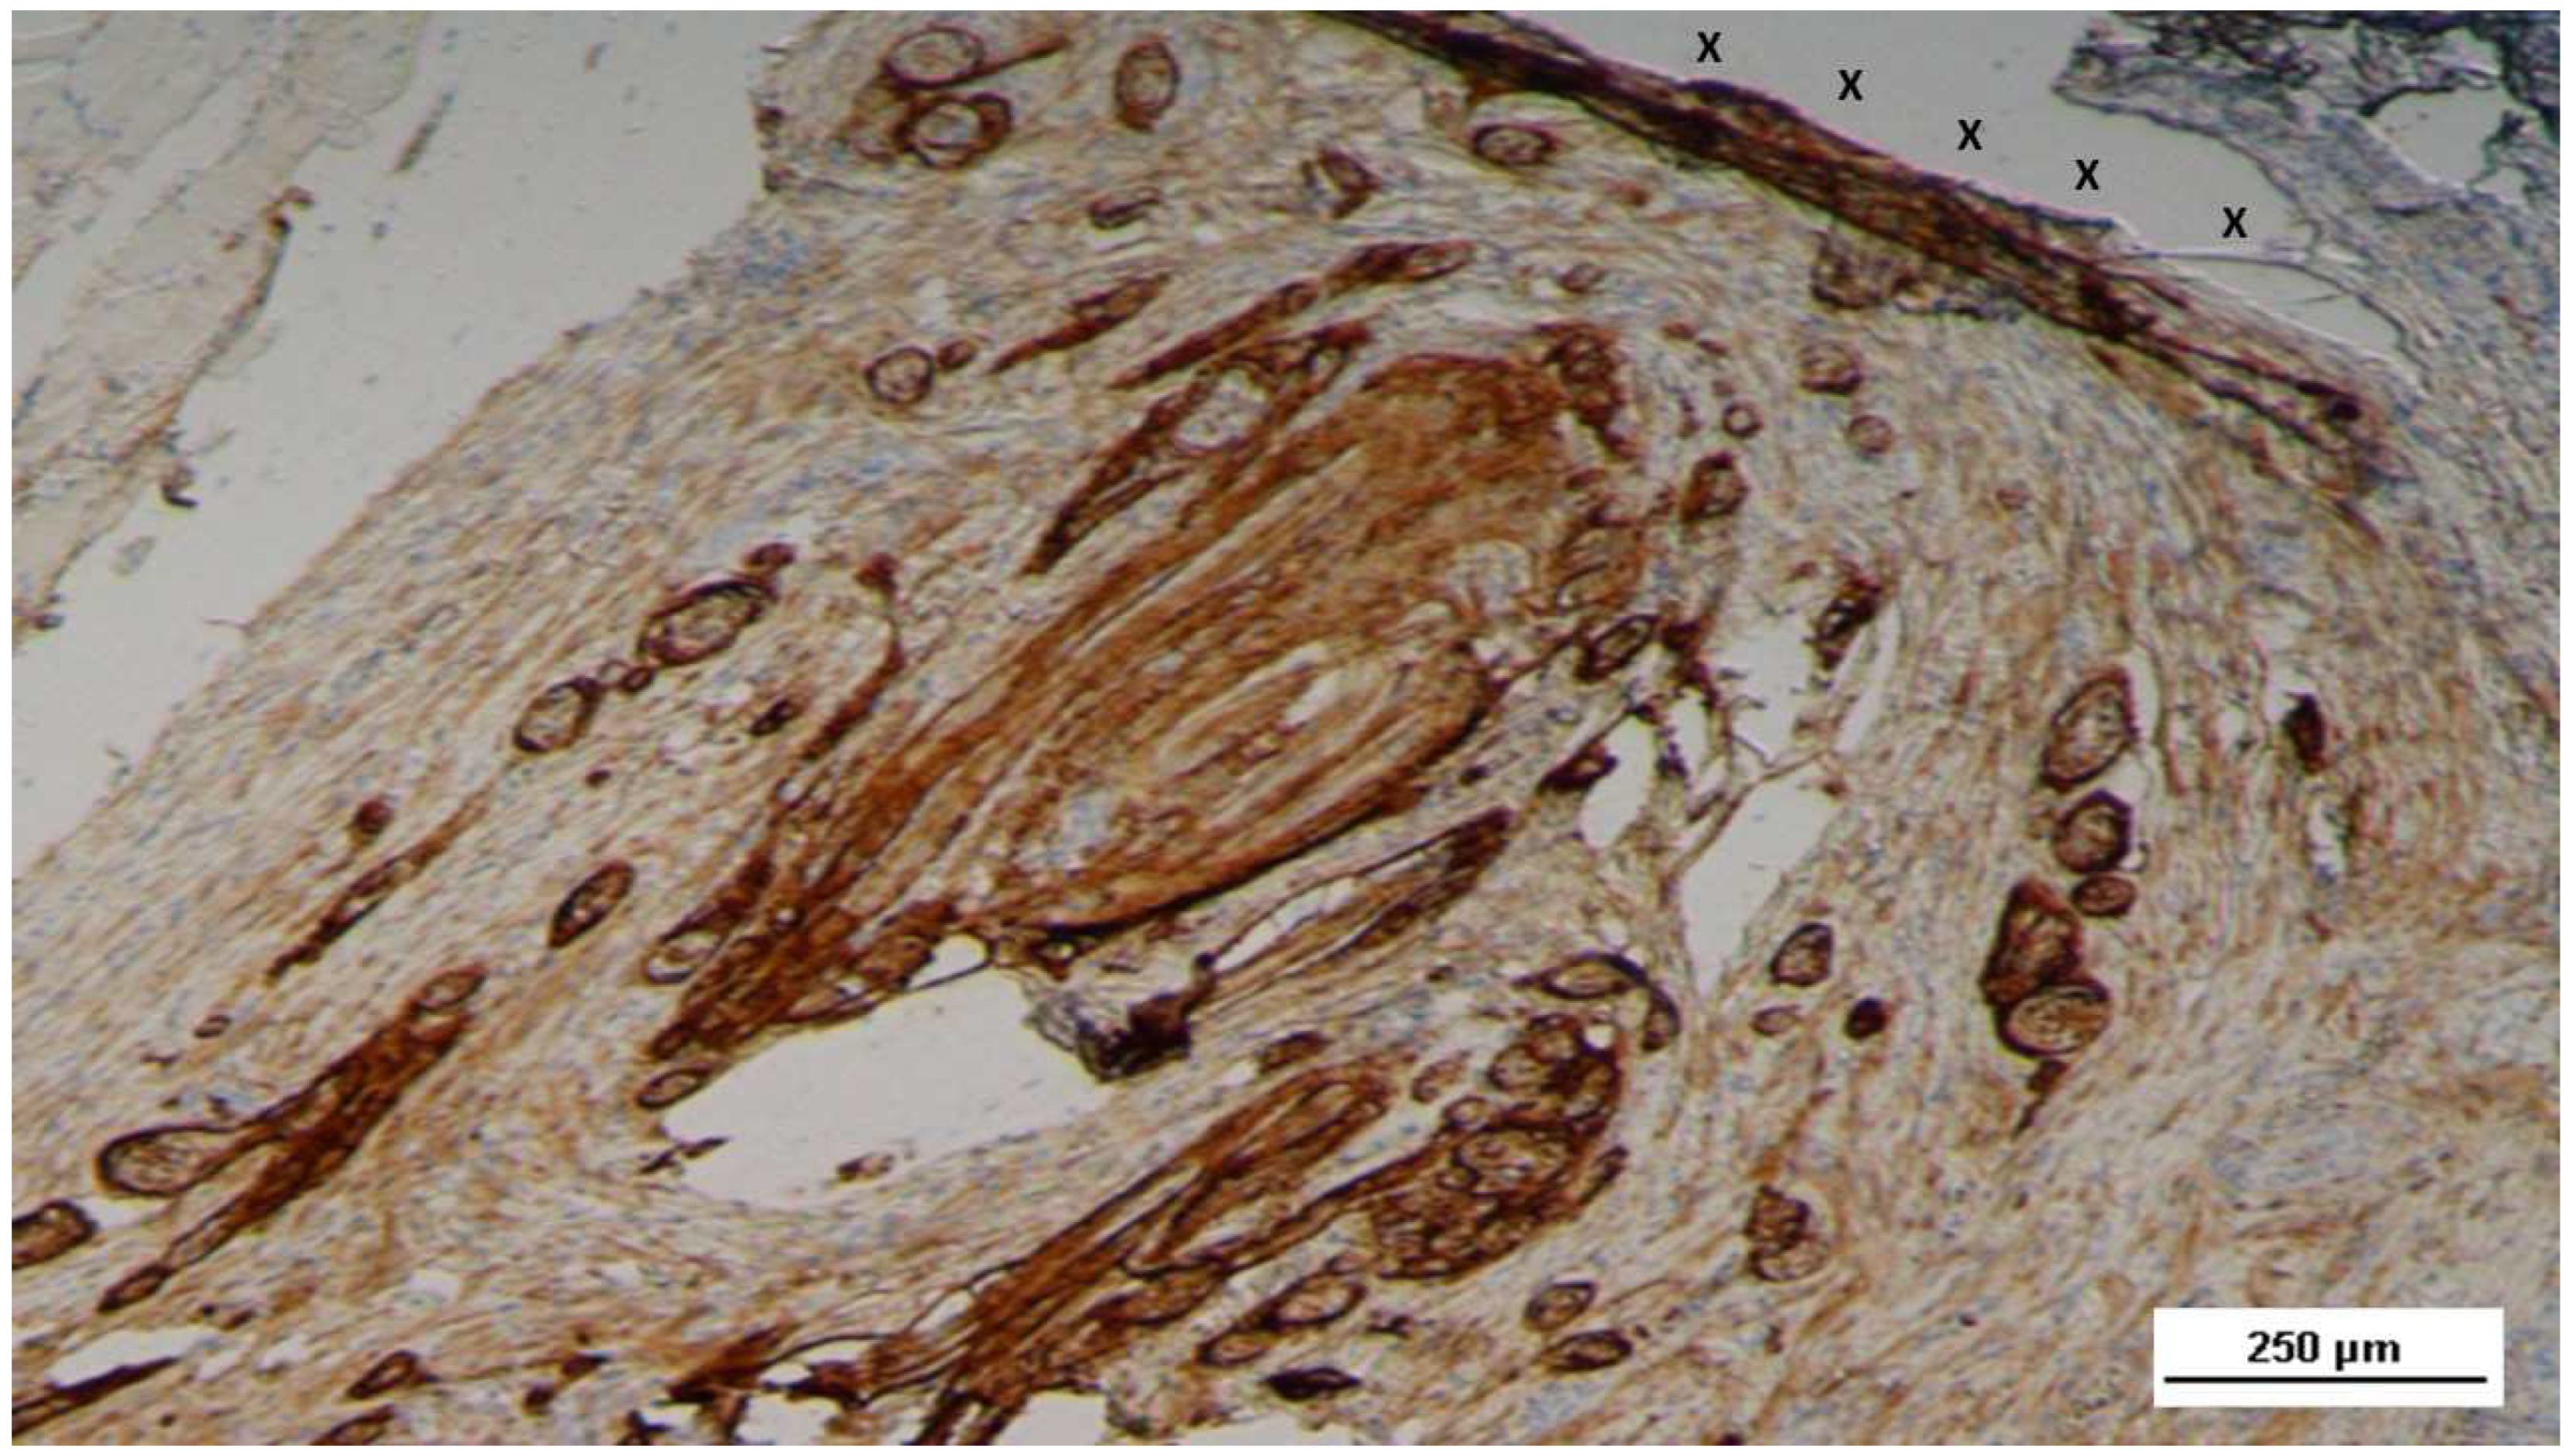

Figure 26. Biopsy sample removed 7 months post-implantation (Long term - LT). Elongated nerve elements (brown staining) in advanced development are present near the 3D scaffold (X). NSE 100X.

In the long-term (LT) stage, compared to earlier phases, there was a marked increase in NGFRp75-positive spindle-shaped cells, located in the cytoplasm and along the membrane of cells near the 3D scaffold (Figure 25).

Numerous mature nerve structures were detected adjacent to the scaffold, signifying advanced nerve growth. These nerves, which developed within the S&S device, displayed substantial increases in both myelin and axon formation, resembling typical human nerve structures in terms of their key components (Figure 26).